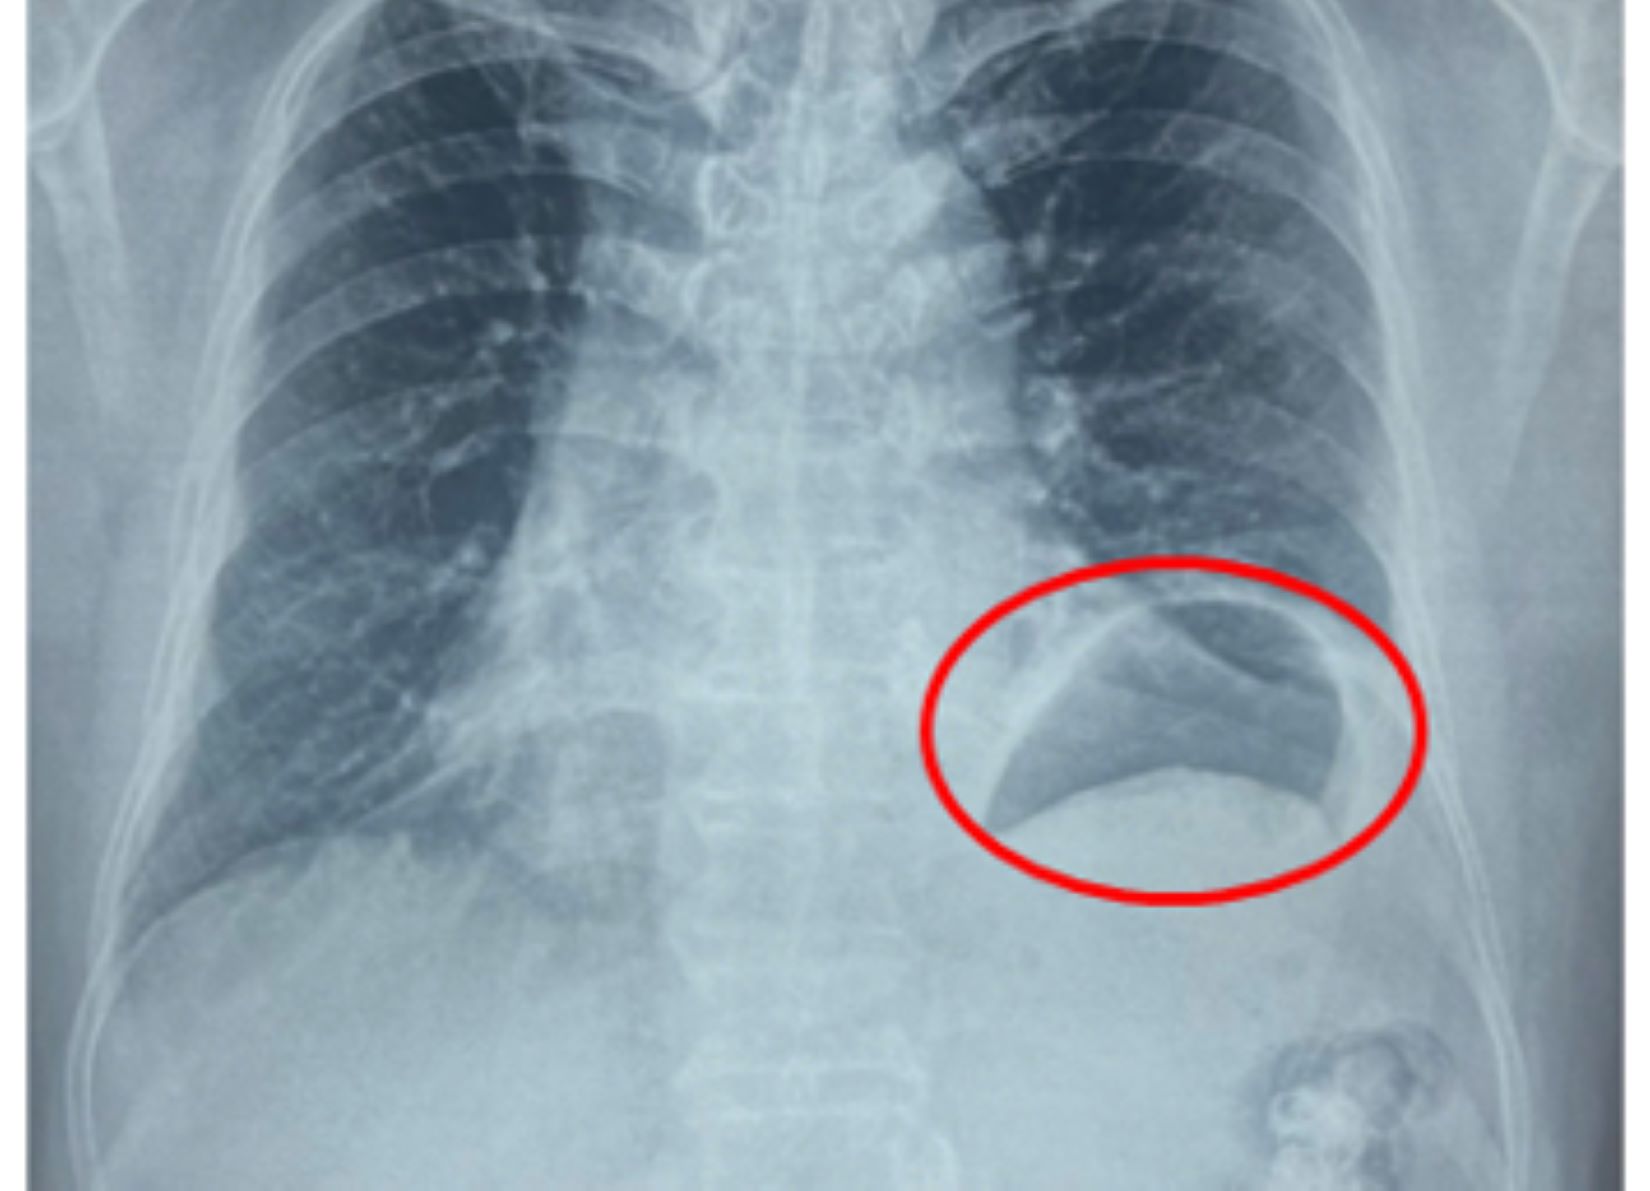

Đến khám tại Bệnh viện Bình Dân, các bác sĩ chẩn đoán ông bị nhão hoành trái với hình ảnh vòm hoành trái nhô cao bất thường. Tình trạng này làm giảm thể tích lồng ngực trái. Đây chính là nguyên nhân khiến ông G bị khó thở khi gắng sức nhiều tháng nay.

Hình ảnh vòm hoành trái cao bất thường do nhão cơ hoành trái làm giảm thể tích lồng ngực trái gây khó thở gắng sức cho bệnh nhân. Ảnh: BVCC